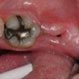

Abscessed Tooth

An abscessed tooth is an infection within a tooth that has spread to the root. Symptoms of an abscessed tooth may include pain, swelling, tenderness, redness, and the presence of a pus-filled lesion on the gum. A dental professional diagnoses an abscessed tooth and dental X-rays may be required. An abscessed tooth is treated with a root canal.